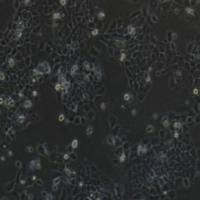

人类星形胶质瘤耐替莫唑胺细胞

Human astroglioma resistant temozolomide cells ,U251MG TMZ U-251MG TMZ

通过外植技术衍生自恶性胶质母细胞瘤肿瘤。

1) 来源:U251胶质瘤耐药筛选

2) 形态:贴壁细胞

细胞耐药诱导过程

待细胞生长稳定后,开始倍增药物诱导剂量,每个剂量保持至细胞可以稳定生长至汇合度达50%以上。递增药物浓度依次为:0.125μg/mL,0.25μg/mL,0.5μg/mL,1μg/mL,2μg/mL,4μg/mL,8μg/mL,16μg/mL。约8个月后,细胞可在16μg/mL TMZ药物浓度下稳定生长,视为耐药细胞株构建成功,并命名为U251 MG/TMZ。